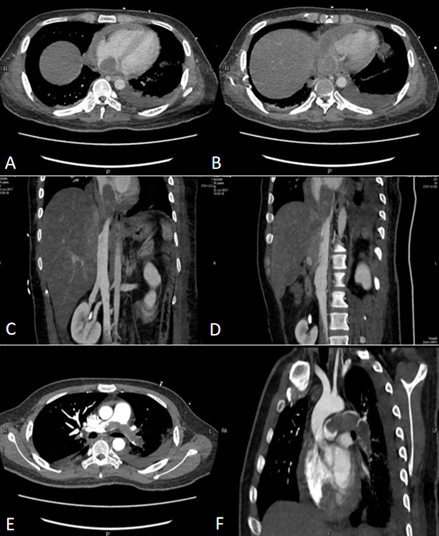

CTA提示(2017年6月15日):①肺动脉主干及左右分支、左上肺动脉中远段、左下肺动脉及其分支,右下肺动脉背段栓塞(图1)。②肝右静脉、中静脉、左静脉及其主要分支、下腔静脉下段及其左右髂静脉未见对比剂充盈;③右肺下叶肺不张;双肺炎症;④双侧胸腔积液、心包积液;⑤盆底少量积液。

图1 2016年6月15日胸部CTA:骑跨型肺动脉栓塞①急性肺动脉血栓栓塞症(中高危);②多部位深静脉血栓形成可能(肝右静脉、中静脉、左静脉、下腔静脉下段、左右髂静脉);③双肺社区获得性肺炎,非重症;④双侧胸腔积液;⑤左侧股骨骨折术后。给予绝对卧床,氧疗,予低分子肝素0.7 ml q12h皮下注射抗凝,完善检查。考虑患者合并双肺社区获得性肺炎,暂经验性予左氧氟沙星0.5 g ivdrip qd抗感染,拟完善检查后行溶栓治疗。经以上处理,目前患者呼吸仍浅促,暂无咯血。继续密切监测病情变化。